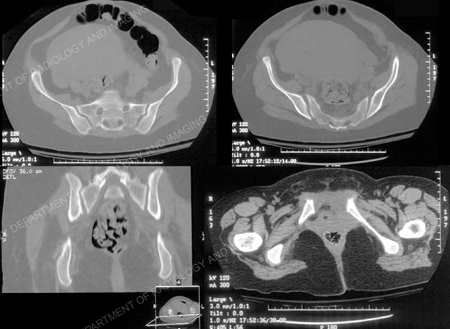

Diagnostic work-up included standard radiographs of the pelvis demonstrating widening of the symphysis pubis of 9 cm and opening of both sacroiliac (SI) joints posteriorly. A CT scan using 2 mm thin cut technique was performed to evaluate the posterior pelvic ring and SI joints. The CT scan demonstrated bilateral sacroiliac joint disruptions. In addition, a MRI scan documented disruption of the pelvic floor and extensive hematoma. Imaging studies revealed an unstable pelvic dislocation with significant symphyseal widening and disruption of the posterior pelvis equivalent to an APC III, or Tile Type C pelvic injury. Open reduction and internal fixation (ORIF) of the pubic symphysis was performed with placement of a contoured 5-hole 3.5 mm pelvic reconstruction plate and screws. Anatomic reduction and stabilization of SI joints were performed using bilateral posterior ilio-sacral screw arthrodesis. Under fluoroscopic control bilateral single 7.3 mm cannulated screws were inserted percutaneously into the body of S1. The perioperative course was unremarkable. She followed up at regular intervals and reported progressive resolution of pain symptoms. The SI screws were removed at 2 years due to mild radiographic evidence of screw loosening. She returned at 2.5 months following hardware removal and reported complete pelvic pain relief and return to pre-injury activities.

CT examination of the pelvis was performed 3 mm contiguous axial sections. Additional sagittal and coronal reformatted images were also obtained (shown in part). CT findings include symphysis diastasis of 9.5 cm and widening of both SI joints. The left SI joint demonstrates widening of 9 mm, the right SI joint 8 mm with posterior subluxation indicating disruption of the entire right sacroiliac joint. A hairline fracture is noted arising from the right pubic symphysis.